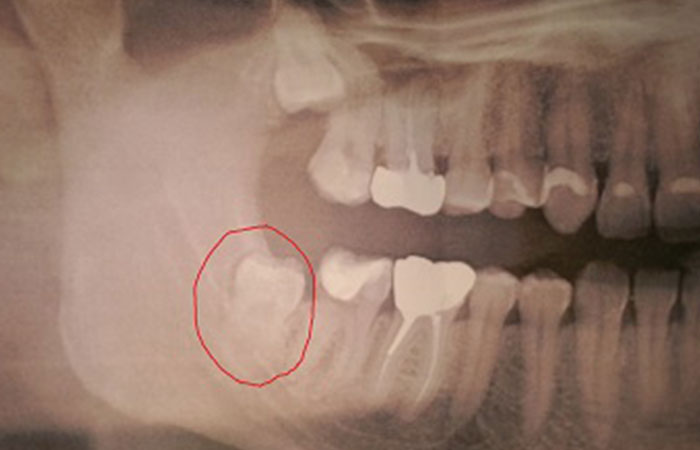

Dents de sagesse